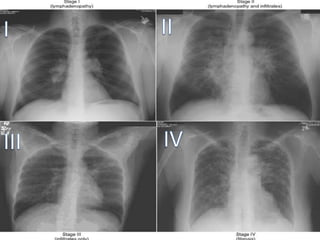

STAGE I

Thoracic Lymphadenopathy.

Normal lung parenchyma. (50%)

STAGE II

Hilar and mediastinal Lymphadenopathy.

Abnormal lung parenchyma. ( 30% )

STAGE III

pulmonary infiltrates with No Lymphadenopathy.

STAGE IV

Extensive pulmonary fibrosis is typically worst in

the upper lobes.

Broad bands of fibrosis in the upper lobes

Permanent lung fibrosis. (20%)